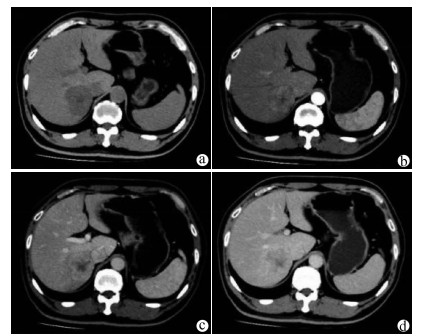

Complete remission after comprehensive treatment of lung metastases following liver cancer surgery: A case report